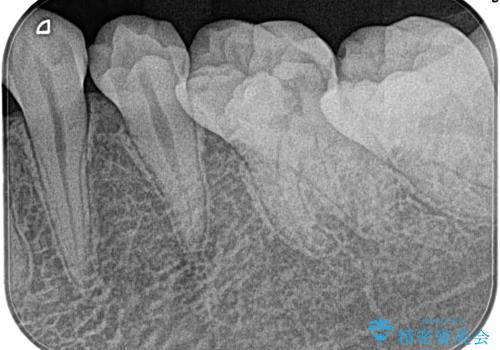

昨晩から激痛。精密根管治療

- 奥歯がズキズキ痛いことを主訴に来院されました。

検査の結果、診断を症候性不可逆性歯髄炎、症候性根尖性歯周炎とし抜髄を行っております。

根管充填はCWCT。

根管形成はマルテンサイト相を有するNi-TIロータリーファイル(NEX MS) 使用。